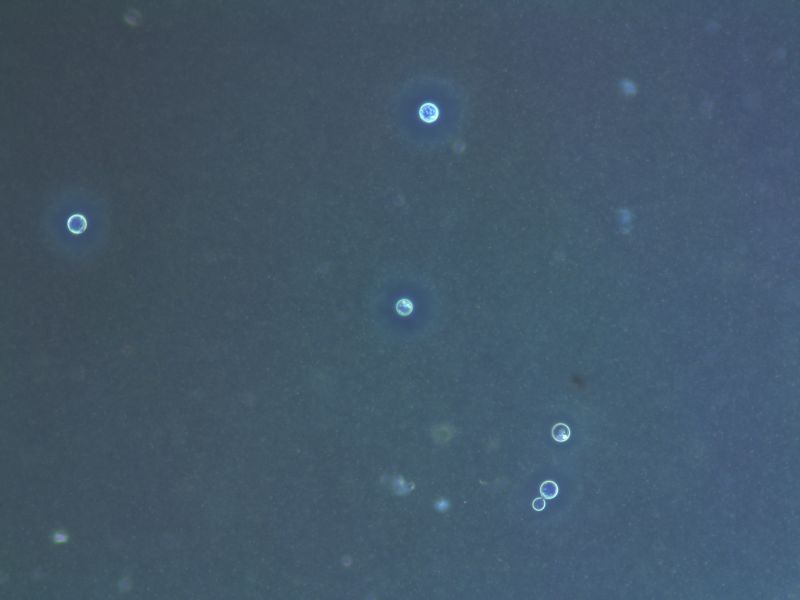

新型隐球菌- 来自穿刺液标本